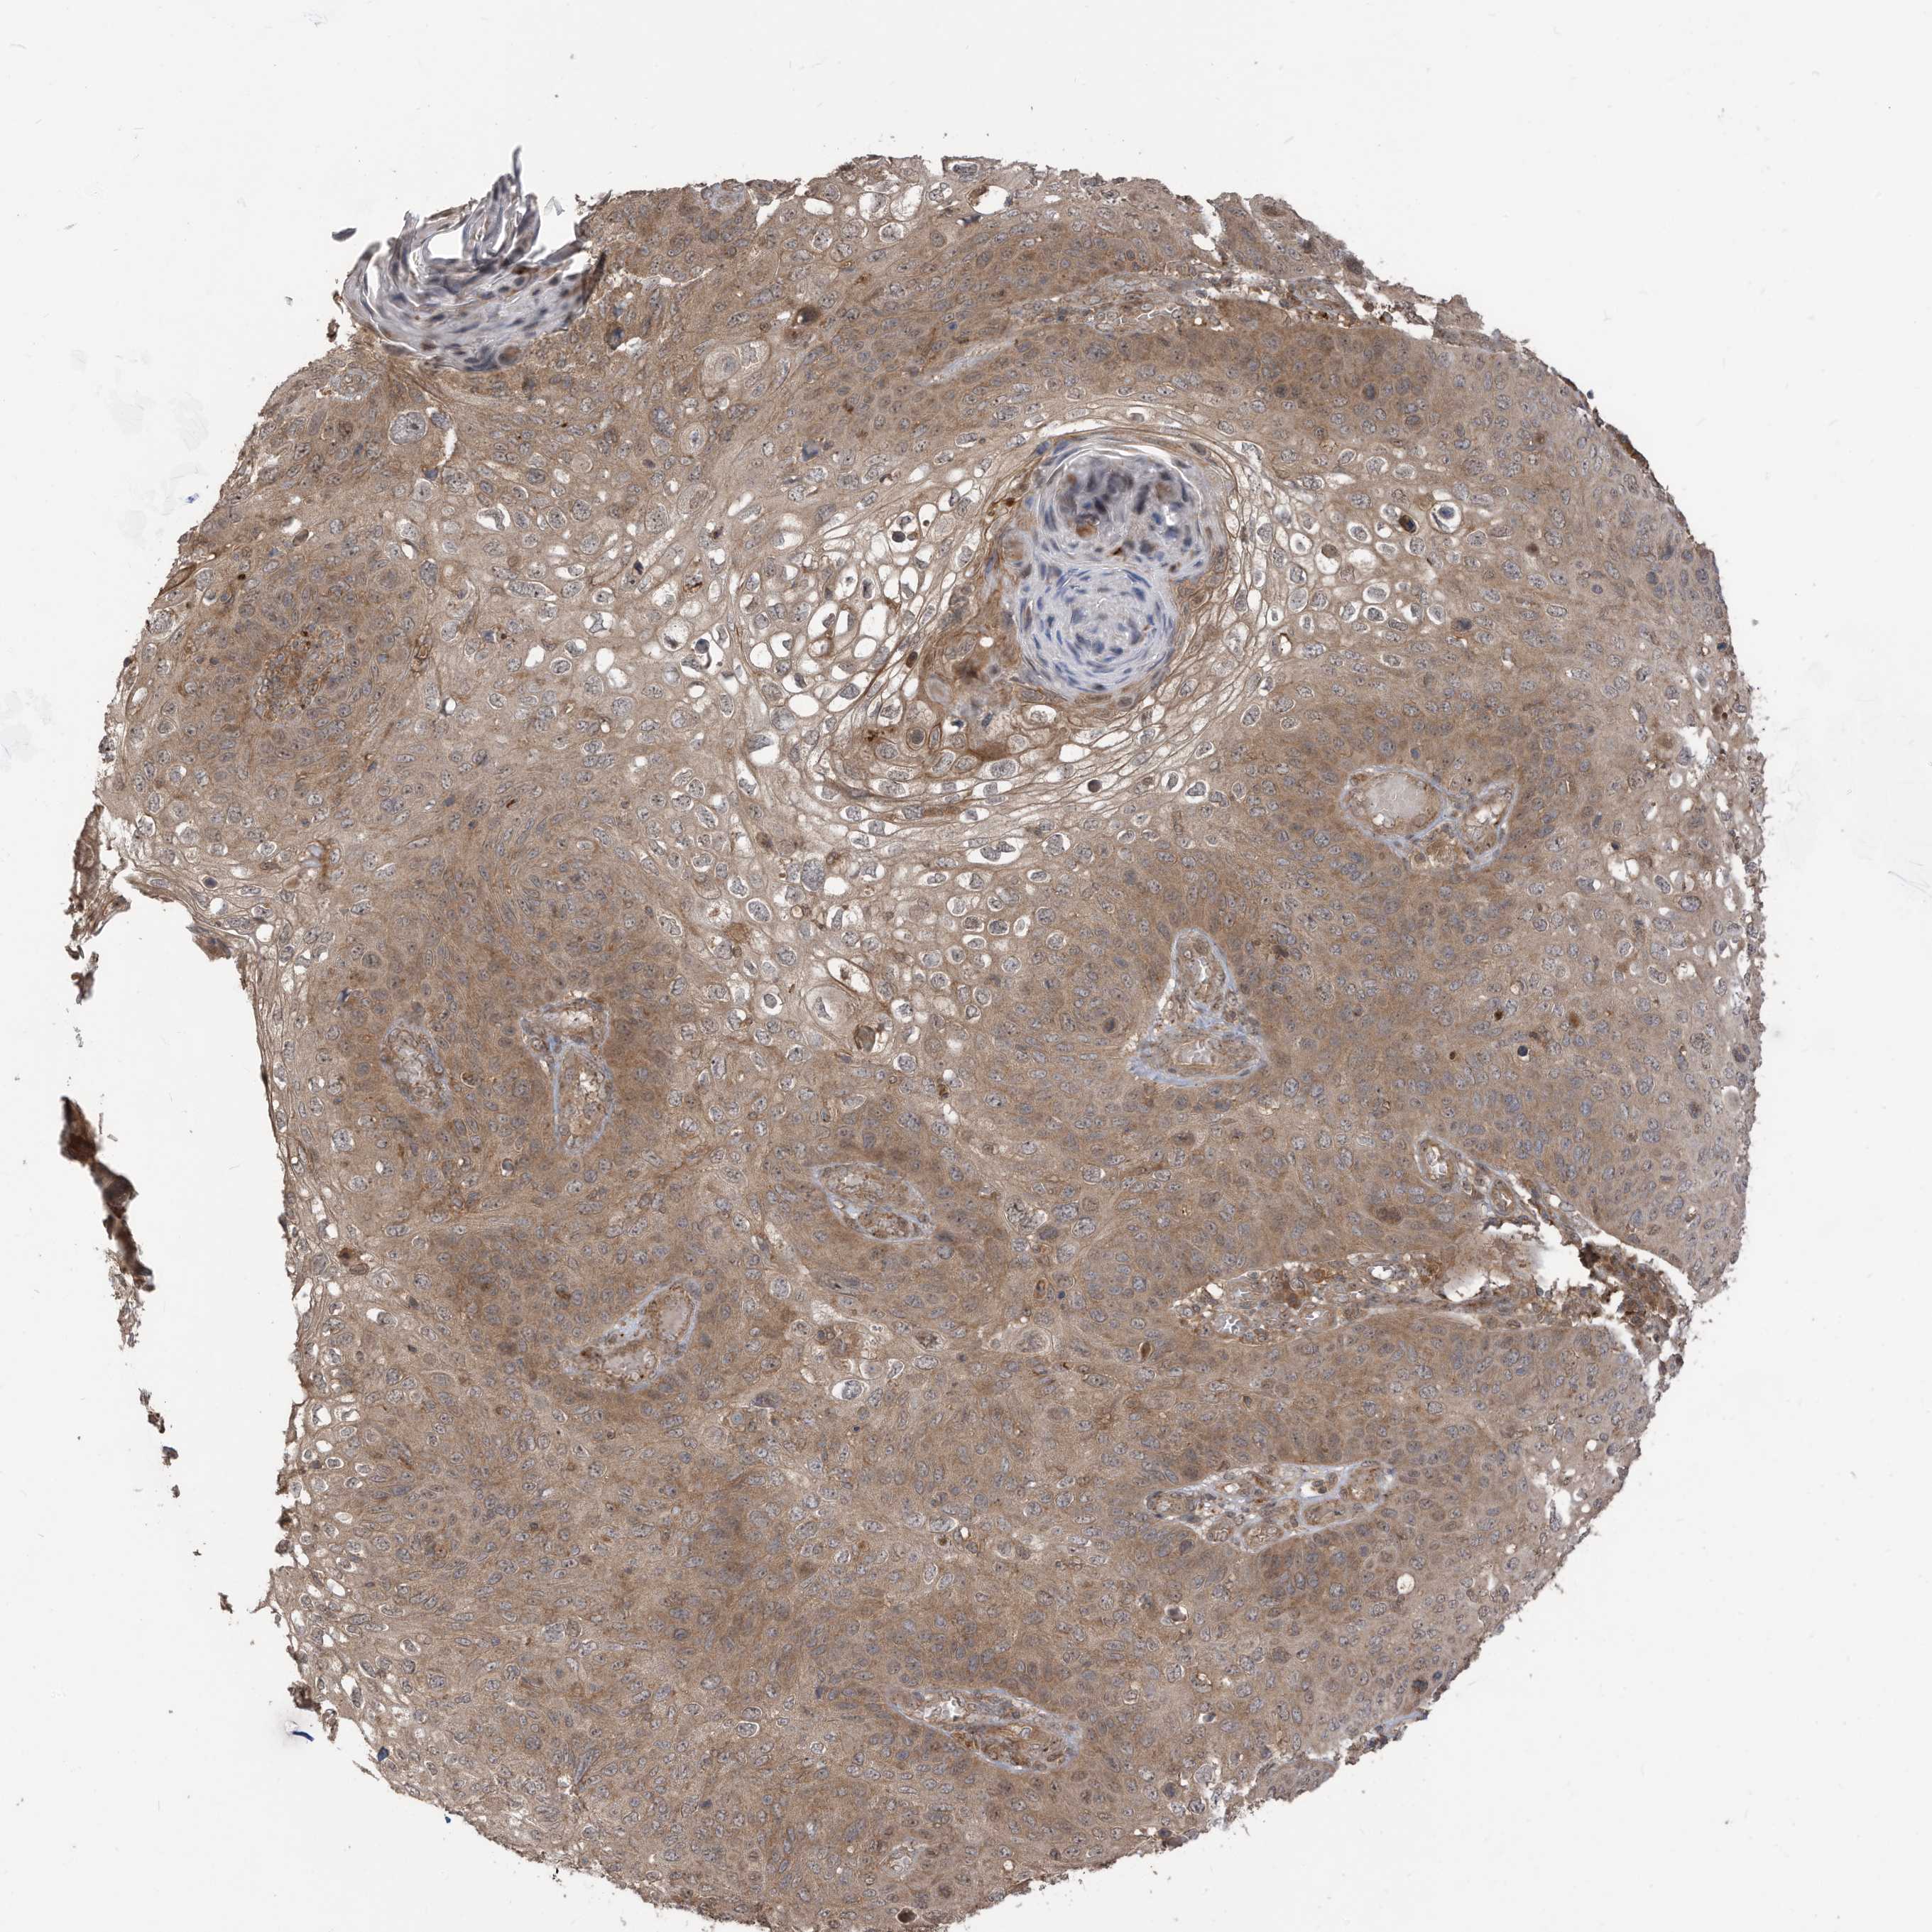

SKIN CANCER - Protein expressioni

A mouse-over function shows sample information and annotation data. Click on an image to view it in a full screen mode. Samples can be filtered based on level of antibody staining by selecting one or several of the following categories: high, medium, low and not detected. The assay and annotation is described here.

Antibody stainingi

Antibody staining in the annotated cell types in the current human tissue is reported as not detected, low, medium, or high, based on conventional immunohistochemistry profiling in selected tissues. This score is based on the combination of the staining intensity and fraction of stained cells.

Each image is clickable and will lead to virtual microscopy that enables deeper exploration of all samples and also displays staining intensity scores, fraction scores and subcellular localization as well as patient and tissue information for each sample.

Antibody HPA034557

Staining

High

Medium

Low

Not detected

Intensity

Strong

Moderate

Weak

Negative

Quantity

>75%

75%-25%

<25%

None

Location

Nuclear

Cytoplasmic/membranous

Cytoplasmic/membranous,nuclear

Squamous cell carcinoma, metastatic, NOS

Squamous cell carcinoma, NOS